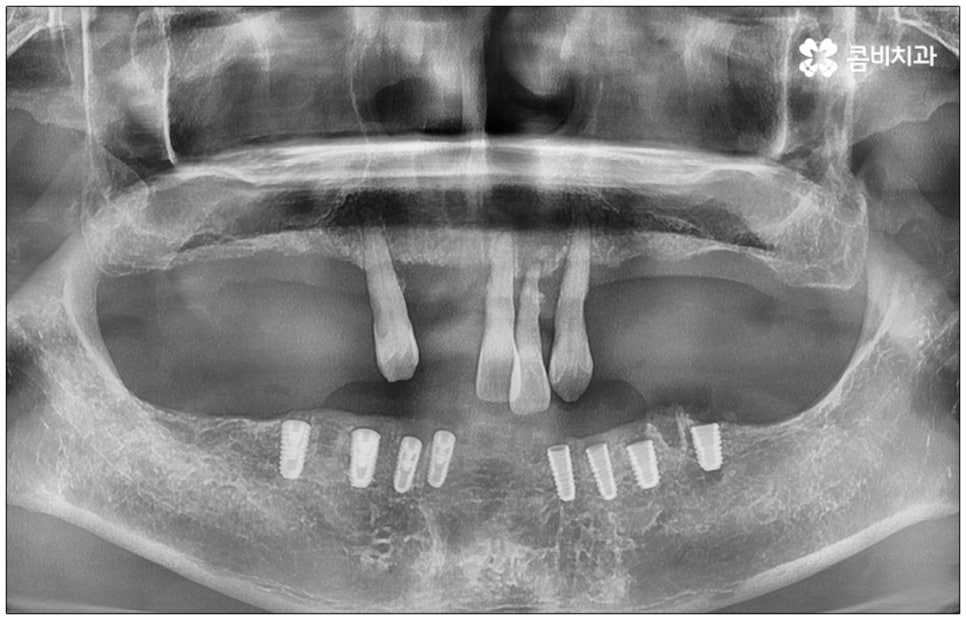

전신 질환을 앓고 있는 분들이나 고령의 환자분들, 다수의 임플란트가 필요한 분들의 경우 컴퓨터 분석을 활용한 임플란트 방식을 통해 도움받아 볼 수 있는데요. 네비게이션 임플란트라고 불리는 이 방식은 첨단 장비를 통해 육안으로 확인하기 어려운 구강 내부의 골조직, 신경 등의 해부학적 구조를 살펴본 다음 3D 모의 수술을 통해 최적의 수술 경로를 찾아내어 가이드를 제작하고 이를 장착하여 그대로 진행하기 때문에 보다 정확하고 안전하게 노인임플란트 수술을 진행할 수 있습니다.

이러한 네비게이션 임플란트 방식은 디지털 기술로 위험 요소를 사전 분석하여 식립 위치와 각도를 보다 정교하게 예측하기 때문에 임플란트 부작용의 발생률을 낮추고 식립 안정성을 높일 수 있는데요. 무절개 또는 최소절개 수술이기 때문에 시술 시간이 짧고 통증이 적으며 회복 기간이 빠르다는 장점을 가지고 있으나 정밀 검진 후 상황상 골유착 과정의 안정성이 떨어질 수 있는 케이스의 경우에는 절개 및 개방 후 수술을 진행하는 것이 좀 더 유리하기 때문에 꼼꼼한 검진, 정확한 판단, 의료진의 높은 숙련도가 굉장히 중요하다고 할 수 있어요.

특히 다수의 치아를 상실했을 때 전체적인 교합, 골조직 및 잇몸 상태, 얼굴형과의 조화 등 모든 부분을 종합적으로 고려하여야 하며 노인임플란트 수술의 경우 다양한 변수가 발생할 수 있기 때문에 이러한 고난도 임플란트 케이스에 노련하게 대처할 수 있도록 풍부한 임상 경험과 노하우를 갖춘 의료진인지, 정밀 검진 기계를 보유하고 있는지, 처음부터 끝까지 철저한 케어 시스템을 갖추고 사후 관리까지 꼼꼼하게 진행하는지 등을 잘 살펴보시고 임플란트 수술을 진행할 치과를 신중하게 선택하시길 권유드리고 있습니다.